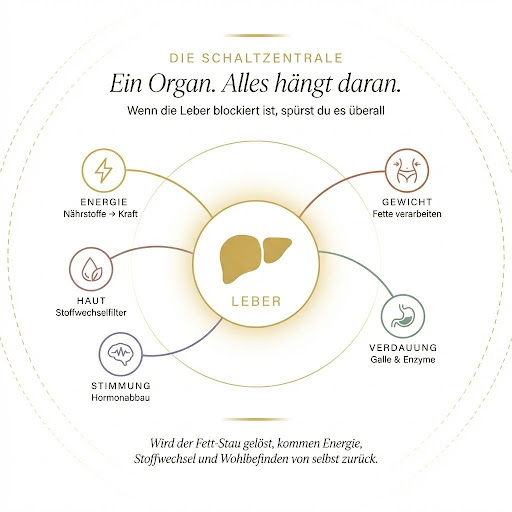

Die Leber ist die Schaltzentrale. Wenn sie durch einen Fett-Stau blockiert ist, leidet nicht nur der Fettstoffwechsel. Alles hängt daran…

- Die Leber wandelt Nährstoffe in Energie um – funktioniert das nicht, bist du müde.

- Sie verarbeitet Fette – funktioniert das nicht, nimmst du zu.

- Sie produziert Galle für die Verdauung – funktioniert das nicht, hast du Blähbauch und Völlegefühl.

- Sie baut Hormone ab – funktioniert das nicht, bist du gereizt und schläfst schlecht.

- Und sie filtert Stoffwechselabfälle – funktioniert das nicht, sieht man es an der Haut.

Was der Leber Komplex bei mir offenbar gemacht hat: Er hat den Stau gelöst. Cholin hat der Leber die Bausteine zurückgegeben, um Fette wieder abzutransportieren. Und sobald dieser Stau sich auflöst, kommt alles andere hinterher. Die Leber arbeitet wieder, der Stoffwechsel läuft, die Energie kommt zurück, das Gewicht geht runter, die Haut wird besser.

Rückblickend macht es absolut Sinn. Aber man muss es einmal selbst erlebt haben, um zu begreifen, wie sehr ein einziges Organ den gesamten Körper beeinflussen kann…